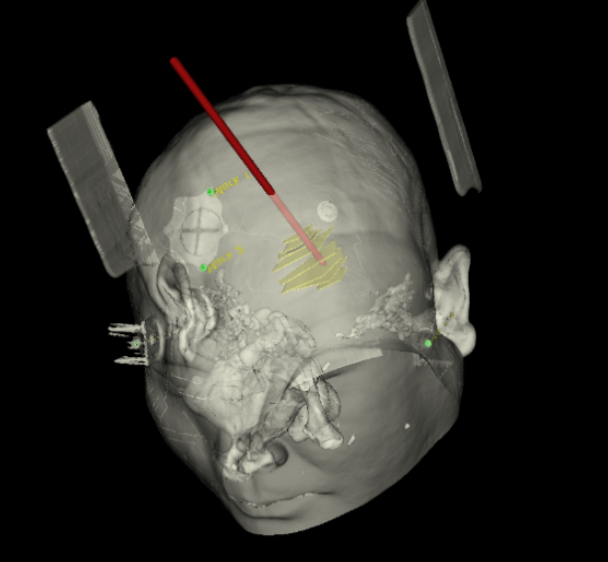

術前韓帥醫(yī)生使用“睿米”制定手術規(guī)劃

手術規(guī)劃在機器人軟件上制定完成